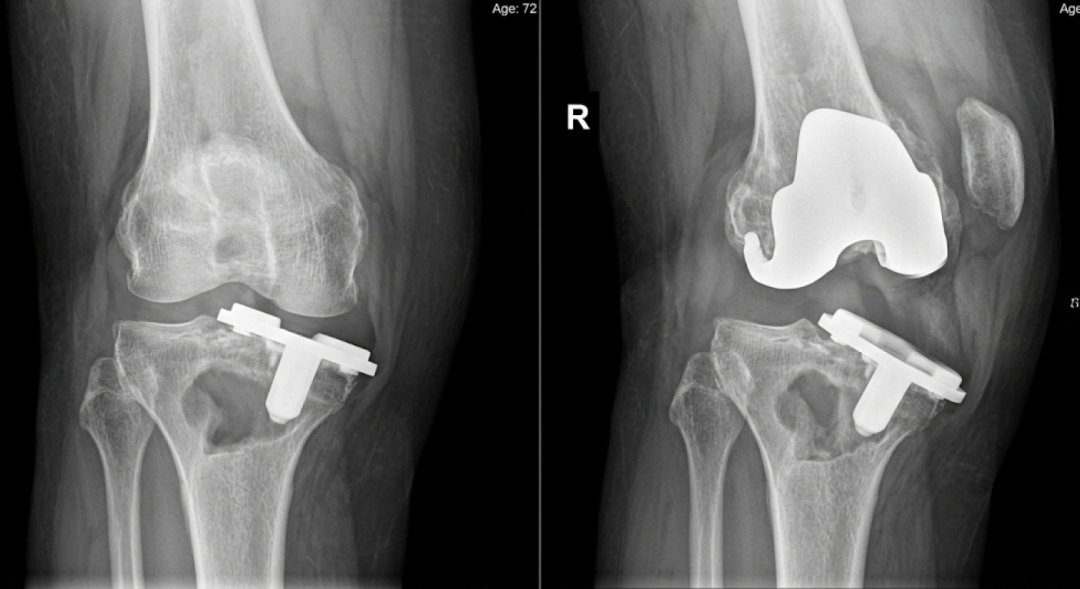

这是使用多年后比较常见的一种情况。简单来说,就是原本与骨结合牢固的假体逐渐出现松动。患者往往会感觉负重时疼痛明显,走远路更难受,有时还会觉得关节不稳。X线检查通常是初步判断的重要手段。

方向四:单髁置换后的变化

如果你当年做的是“单髁置换”(即只换了膝盖受损最重的一侧),而不是全膝关节置换,那么随着时间推移,其他原本健康或者退变不明显的那部分骨骼可能也出现了老化或者继续退变,这时候可能需要考虑将原来的单髁“升级”为全膝置换。松动、磨损、感染这三类问题,单髁置换的患者也同样需要关注。